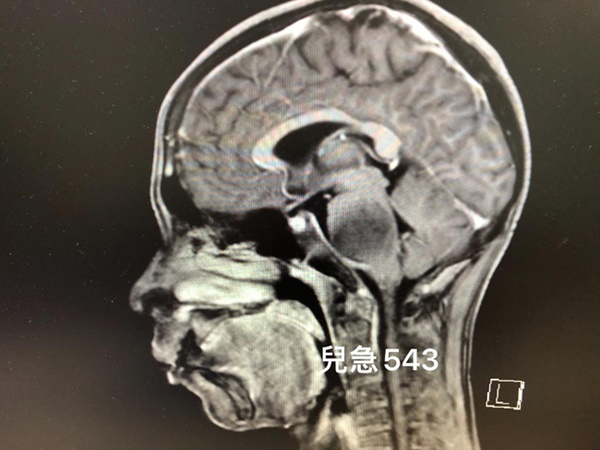

Mới đây, bác sĩ Ngô Xương Đằng, khoa nhi, bệnh viện Linkou Chang Gung Memorial Hospital, Đài Loan, chia sẻ về trường hợp một bệnh nhi nhập viện trong tình trạng thường xuyên nhức đầu, đi đứng mất thăng bằng, liệt mặt, nuốt khó, giảm thị lực, chân tay yếu. Kết quả chụp CT não phát hiện bệnh nhi mắc bệnh u não.

Kết quả chụp CT não phát hiện bệnh nhi mắc bệnh u não.